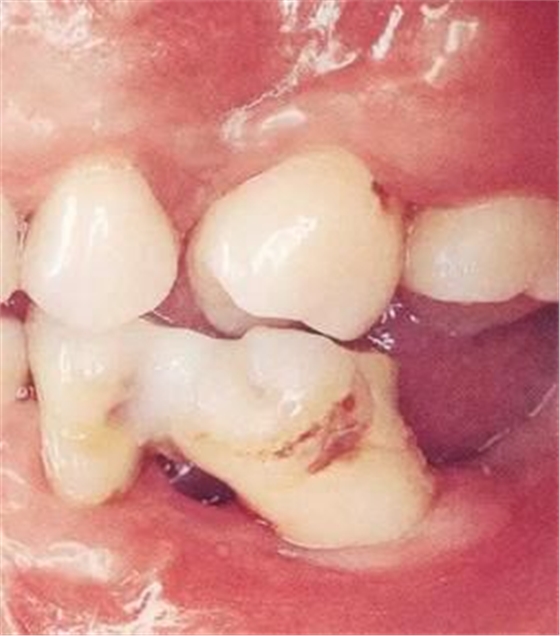

▲圖2

牙位異常例②。牙體傾斜。